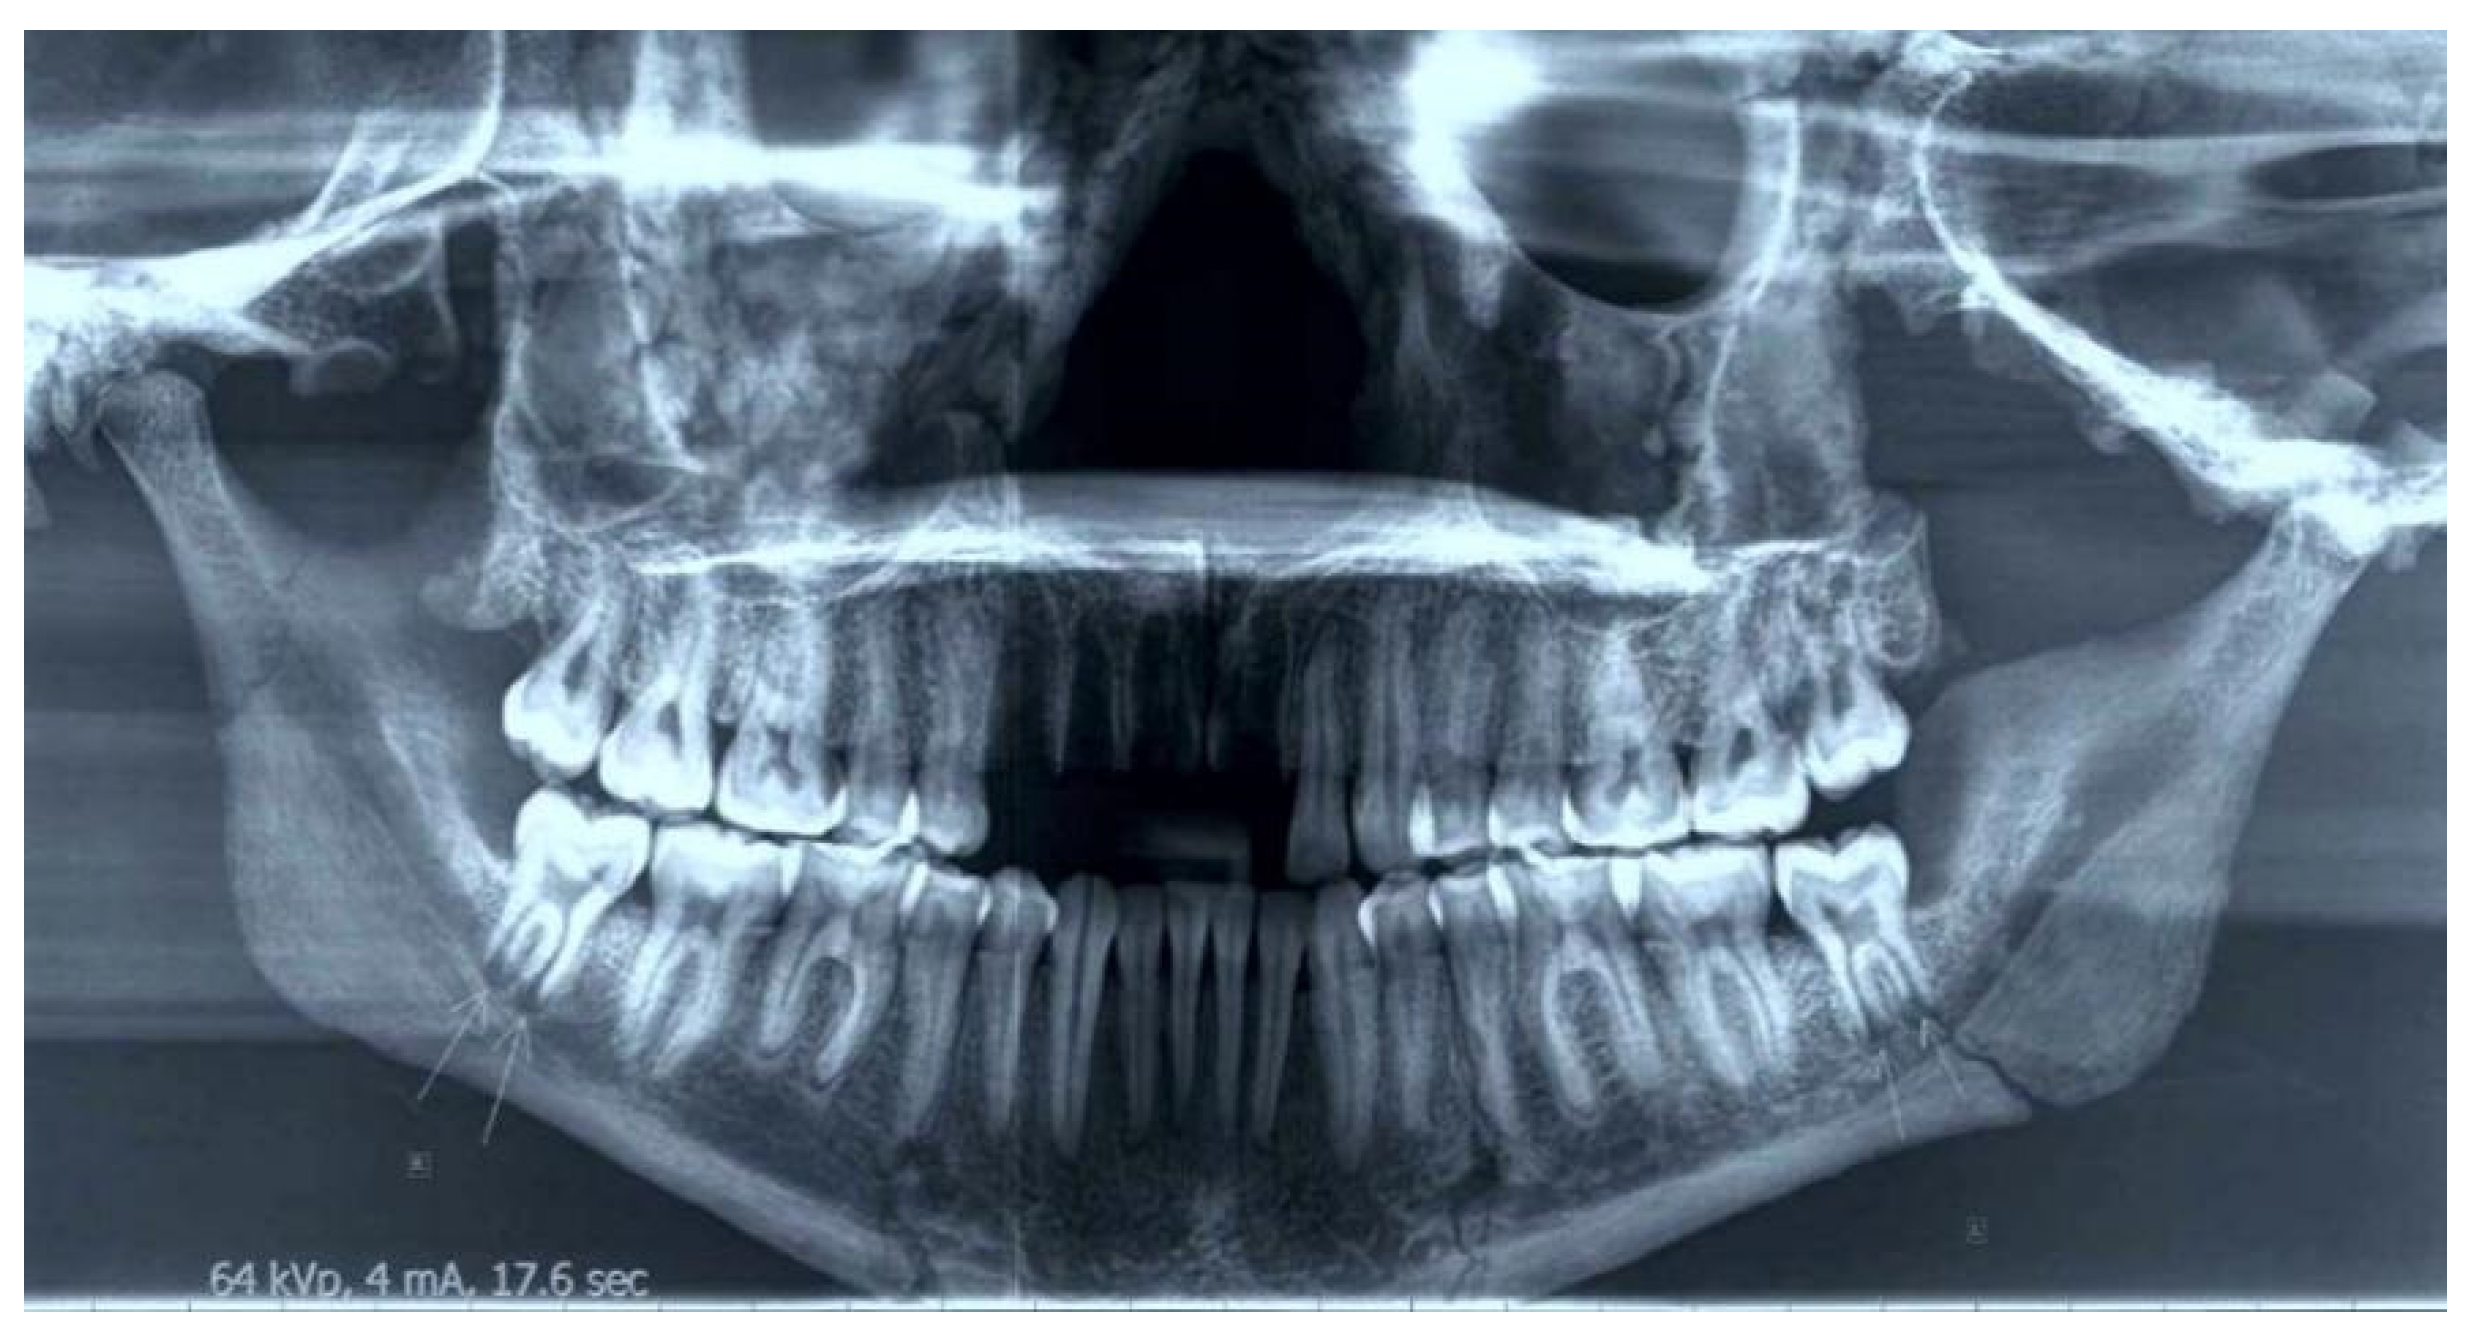

3.4. Dental Pathology

3.5. 3D Modeling